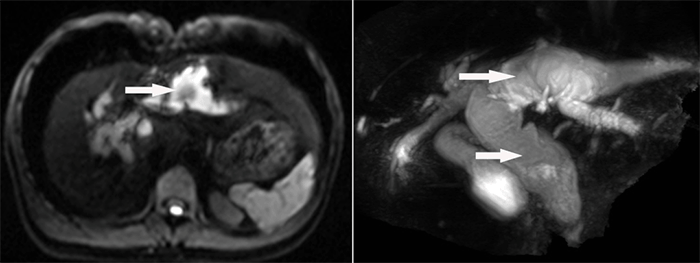

MRCP显示肝内外胆管囊状病变及胆管结石

经科室内全体医生讨论,先天性胆管扩张症的并发症发生率高达20~60%,且有一定癌变率,癌变率随患者年龄增大而递增。该患者病变广泛并波及肝内外胆管,除肝外胆管显著囊状扩张外,肝内胆管囊状扩张以左半肝内胆管显著并胆管结石,患者手术指针明确。